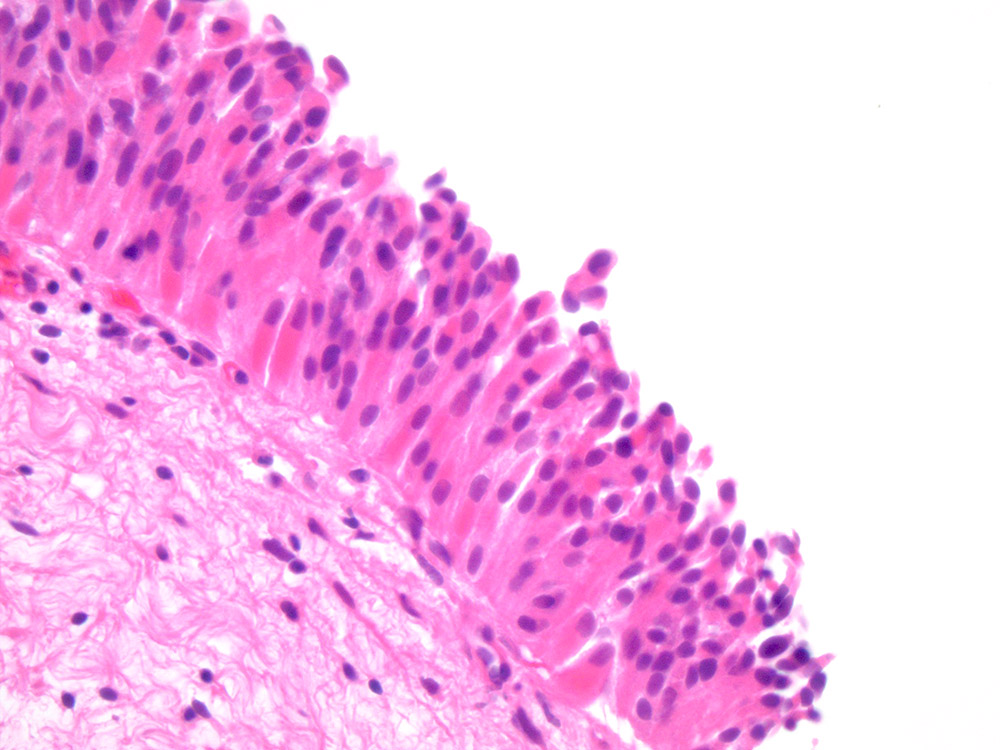

Consensus grade: Atypia/dysplasia

Case description (by case creator):

Flat lesion